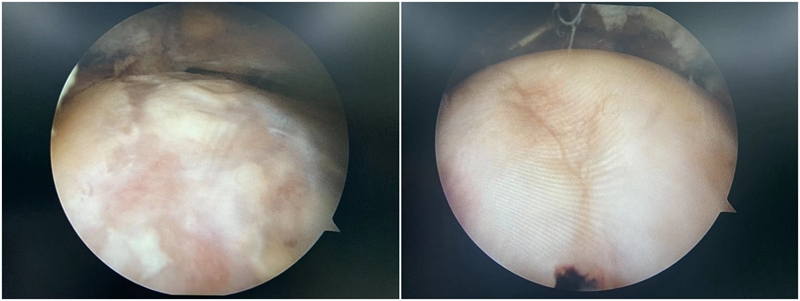

3.软骨损伤的处理:髋关节撞击综合征患者除了常常导致髋关节盂唇的损伤之外,还常常造成髋关节软骨的损伤,而且髋关节软骨损伤的部位也常常发生在髋臼的前方。目前对于任一关节的软骨损伤治疗都是难点,对于髋关节这样的负重关节更是如此。对于怀疑存在软骨损伤患者,则应早期进行手术治疗,尽可能避免髋关节退变的结局。

图11 撞击导致软骨损伤